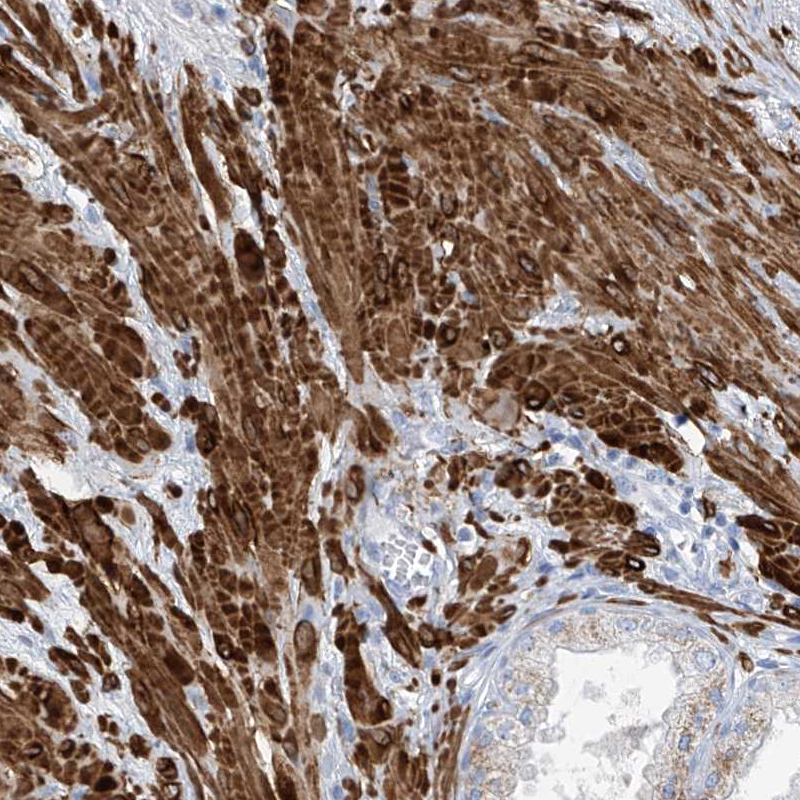

Immunohistochemical staining of human prostate shows strong cytoplasmic positivity in smooth muscle cells.